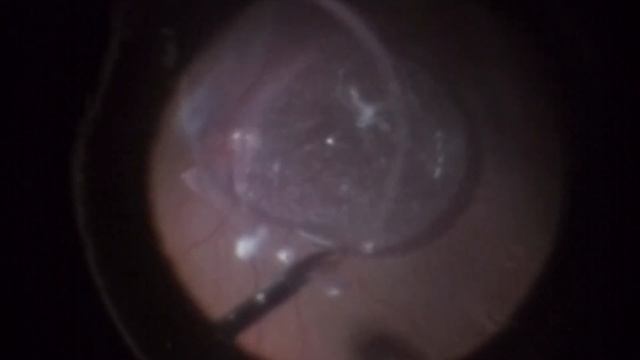

Dislocated IOL - Pars plana vitrectomy and IOL Exchange смотреть онлайн

03:56

Dislocated IOL - Pars plana vitrectomy and IOL Exchange

JS: вдохновение от Мастеров 16 просмотров